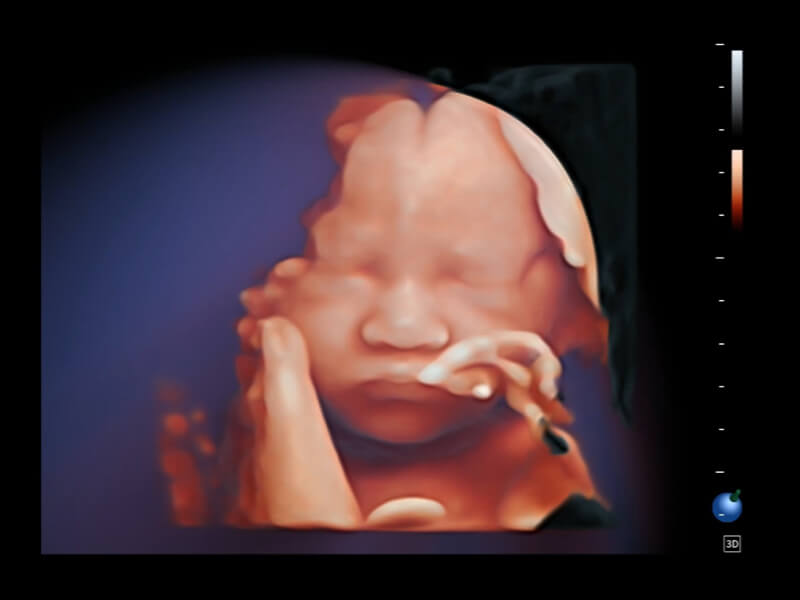

作为开立医疗全新打造的超高端旗舰超声产品,从探头抬起唤醒开启扫查到多维探头发射接收,通过先进的场成像发射、自适应聚合重建等技术,基于RF Data原始射频数据在图像生成、高端功能等方面实现突破,为妇产科、儿科提供全方位临床解决方案。

梦溪®P80以“关爱女性”为基石,提供全方位的解决方案,量身定制以满足女性的健康需求,涵盖妇科、生殖健康检查、产前筛查及产后康复等领域。